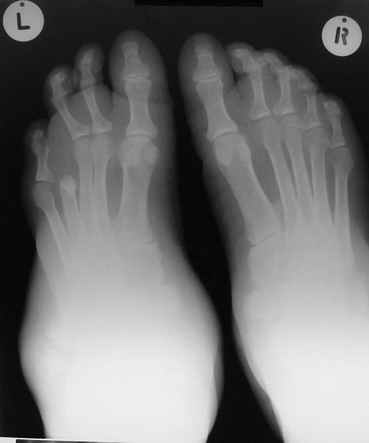

Уажаемые коллеги,представленные рентгенограмммы я показывал на нашем х-рей митинге - они были встречены с большим интересом.. Ну, ещё бы - я сам эту патологии встречал раза три за всю свою долгую жизнь:

После меня выступал с новыми находками для своей коллекции Эмануэл Лакью Тесема, хирург-ортопед из Эфиопии: Мне понравились его находки:

Кто шустрый - при какой патологии встречается так называемые "суставы Шарко"?Второе приобретение доктора Эмануэла мне понравилось своим романтическим названием: Candle bone - <кость-в-виде-оплывающей-свечи> : Просто редкая патология:

VR>Второе приобретение доктора Эмануэла мне понравилось своим романтическим названием: Candle bone - <кость-в-виде-оплывающей-свечи> : Просто редкая патология:

Остеосклероз при этом заболевании захватывает не всю кость по окружности, а простирается слегка волнистой

полосой вдоль длинной оси конечности (рис. 223, К), переходя через линию суставов на другие кости. Таким образом,

может оказаться пораженной целая верхняя или нижняя конечность или больший или меньший ее периферический участок,

например, часть лопатки, полуцилиндр плечевой кости, часть цилиндра лучевой кости и скелет II пальца вместе с

лежащими по этой оси участками запястных костей или же часть - медиальная или латеральная - бедренной,

болынеберцовой кости с продолжением и расширением процесса на предплюсневые и плюсневые кости и соответствующие

по длиннику фаланги одного или нескольких, но никогда не всех пальцев. Описавшие эту болезнь в 1922 г. Жоани

(Joanny) и Лери (Leri) сравнивают остеосклеротические полосы с картиной, напоминающей стекающий со свечи и

застывающий стеарин или воск, отсюда и название "мелореостоз" - "стекающая вдоль конечности кость".

Наконец, важным внешним клиническим выражением мелореостоза могут служить деформативные явления, из которых

раньше всего бросаются в глаза осевые уклонения в сторону одного из пальцев кисти.